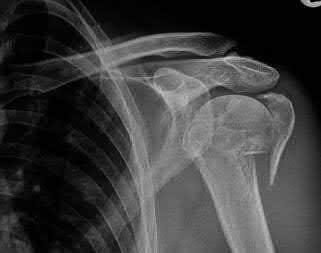

Question 3:

A 15-year-old boy presents with a permeative lytic lesion in the femoral diaphysis with aggressive periosteal reaction ('onion skinning'). Biopsy reveals uniform small round blue cells. Cytogenetic analysis of this tumor will most likely demonstrate which of the following translocations?

Correct Answer: t(11;22)

Explanation:

The clinical and radiographic description is classic for Ewing sarcoma. The characteristic cytogenetic abnormality is a balanced translocation t(11;22)(q24;q12), which fuses the EWS gene on chromosome 22 with the FLI1 gene on chromosome 11. This is seen in approximately 85-90% of Ewing sarcomas. t(9;22) is the Philadelphia chromosome (CML), t(X;18) is seen in synovial sarcoma, t(2;13) in alveolar rhabdomyosarcoma, and t(12;16) in myxoid liposarcoma.